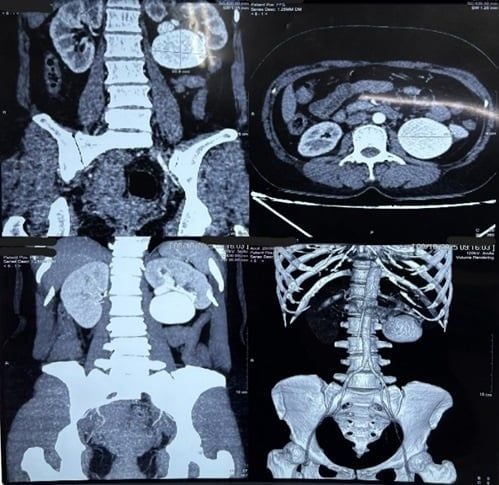

Hình 1. Hình CT-Scan trước mổ (khối phình động mạch thận lớn bên trái, mũi tên trắng)

Qua thăm khám và hỏi bệnh sử thì ghi nhận người bệnh không chấn thương hay từng can thiệp ngoại khoa trước đây, làm thêm các xét nghiệm hình ảnh chuyên sâu thì được chẩn đoán phình thông động tĩnh mạch thận trái bẩm sinh. Với mục tiêu bảo tồn thận, đảm bảo an toàn và xâm lấn tối thiểu trên người bệnh các bác sĩ của Bệnh viện Nhân Dân 115 gồm hai chuyên khoa Ngoại niệu - ghép thận và Đơn vị Can thiệp mạch máu - Khoa Chẩn đoán hình ảnh đã hội chẩn. Với trường hợp này người bệnh có kích thước khối phình rất lớn 6x6x5 cm kèm hình thái phức tạp, việc nút mạch bằng can thiệp mạch máu thận là không an toàn và khả thi. Để đảm bảo an toàn và tổn thương xâm lấn ít nhất cho người bệnh, PGS.TS.BS.Trương Hoàng Minh (Trưởng khoa Ngoại niệu - Ghép thận) đã đưa ra phương pháp phẫu thuật nội soi sau phúc mạc nhằm loại bỏ túi phình và bảo tồn thận.